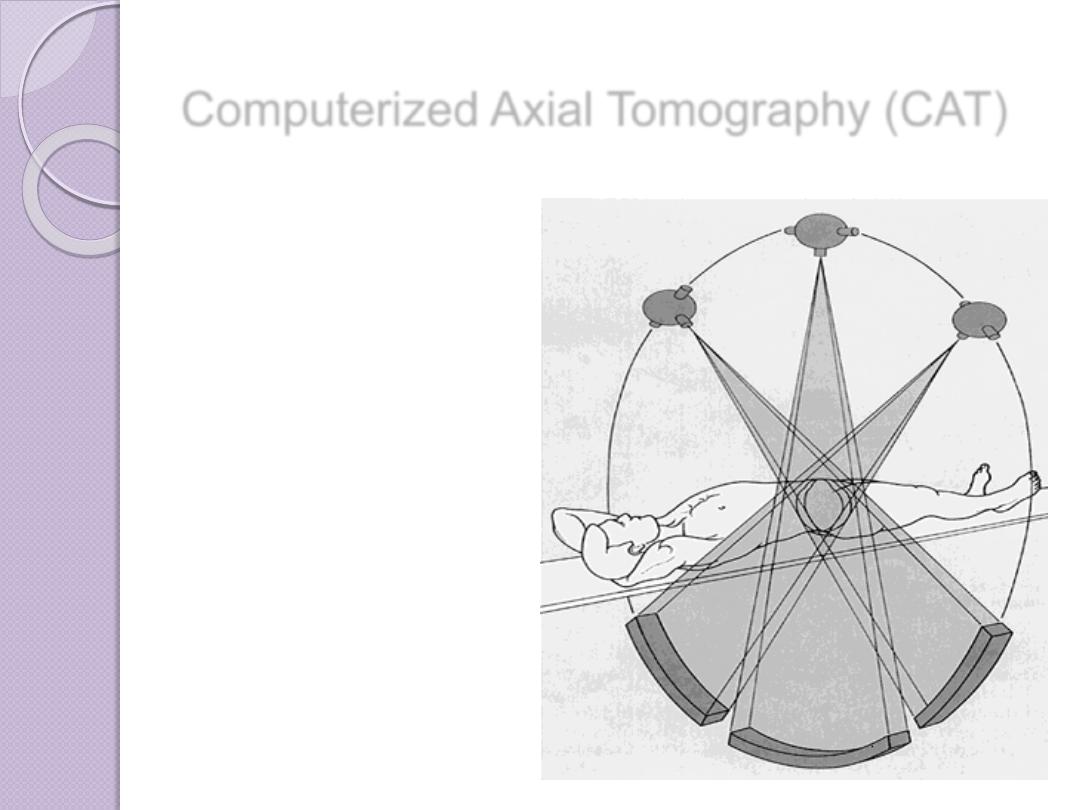

Computerized Axial Tomography (CAT)

In this process a small beam of x-

ray is passed through a plane of the

body while the x-ray tube moves in

an arc or a circle around the body

Computerized Axial Tomography (CAT)

The amount of radiation absorbed

by different elements of the chosen

plane varies according to X ray

absorptions by different tissues